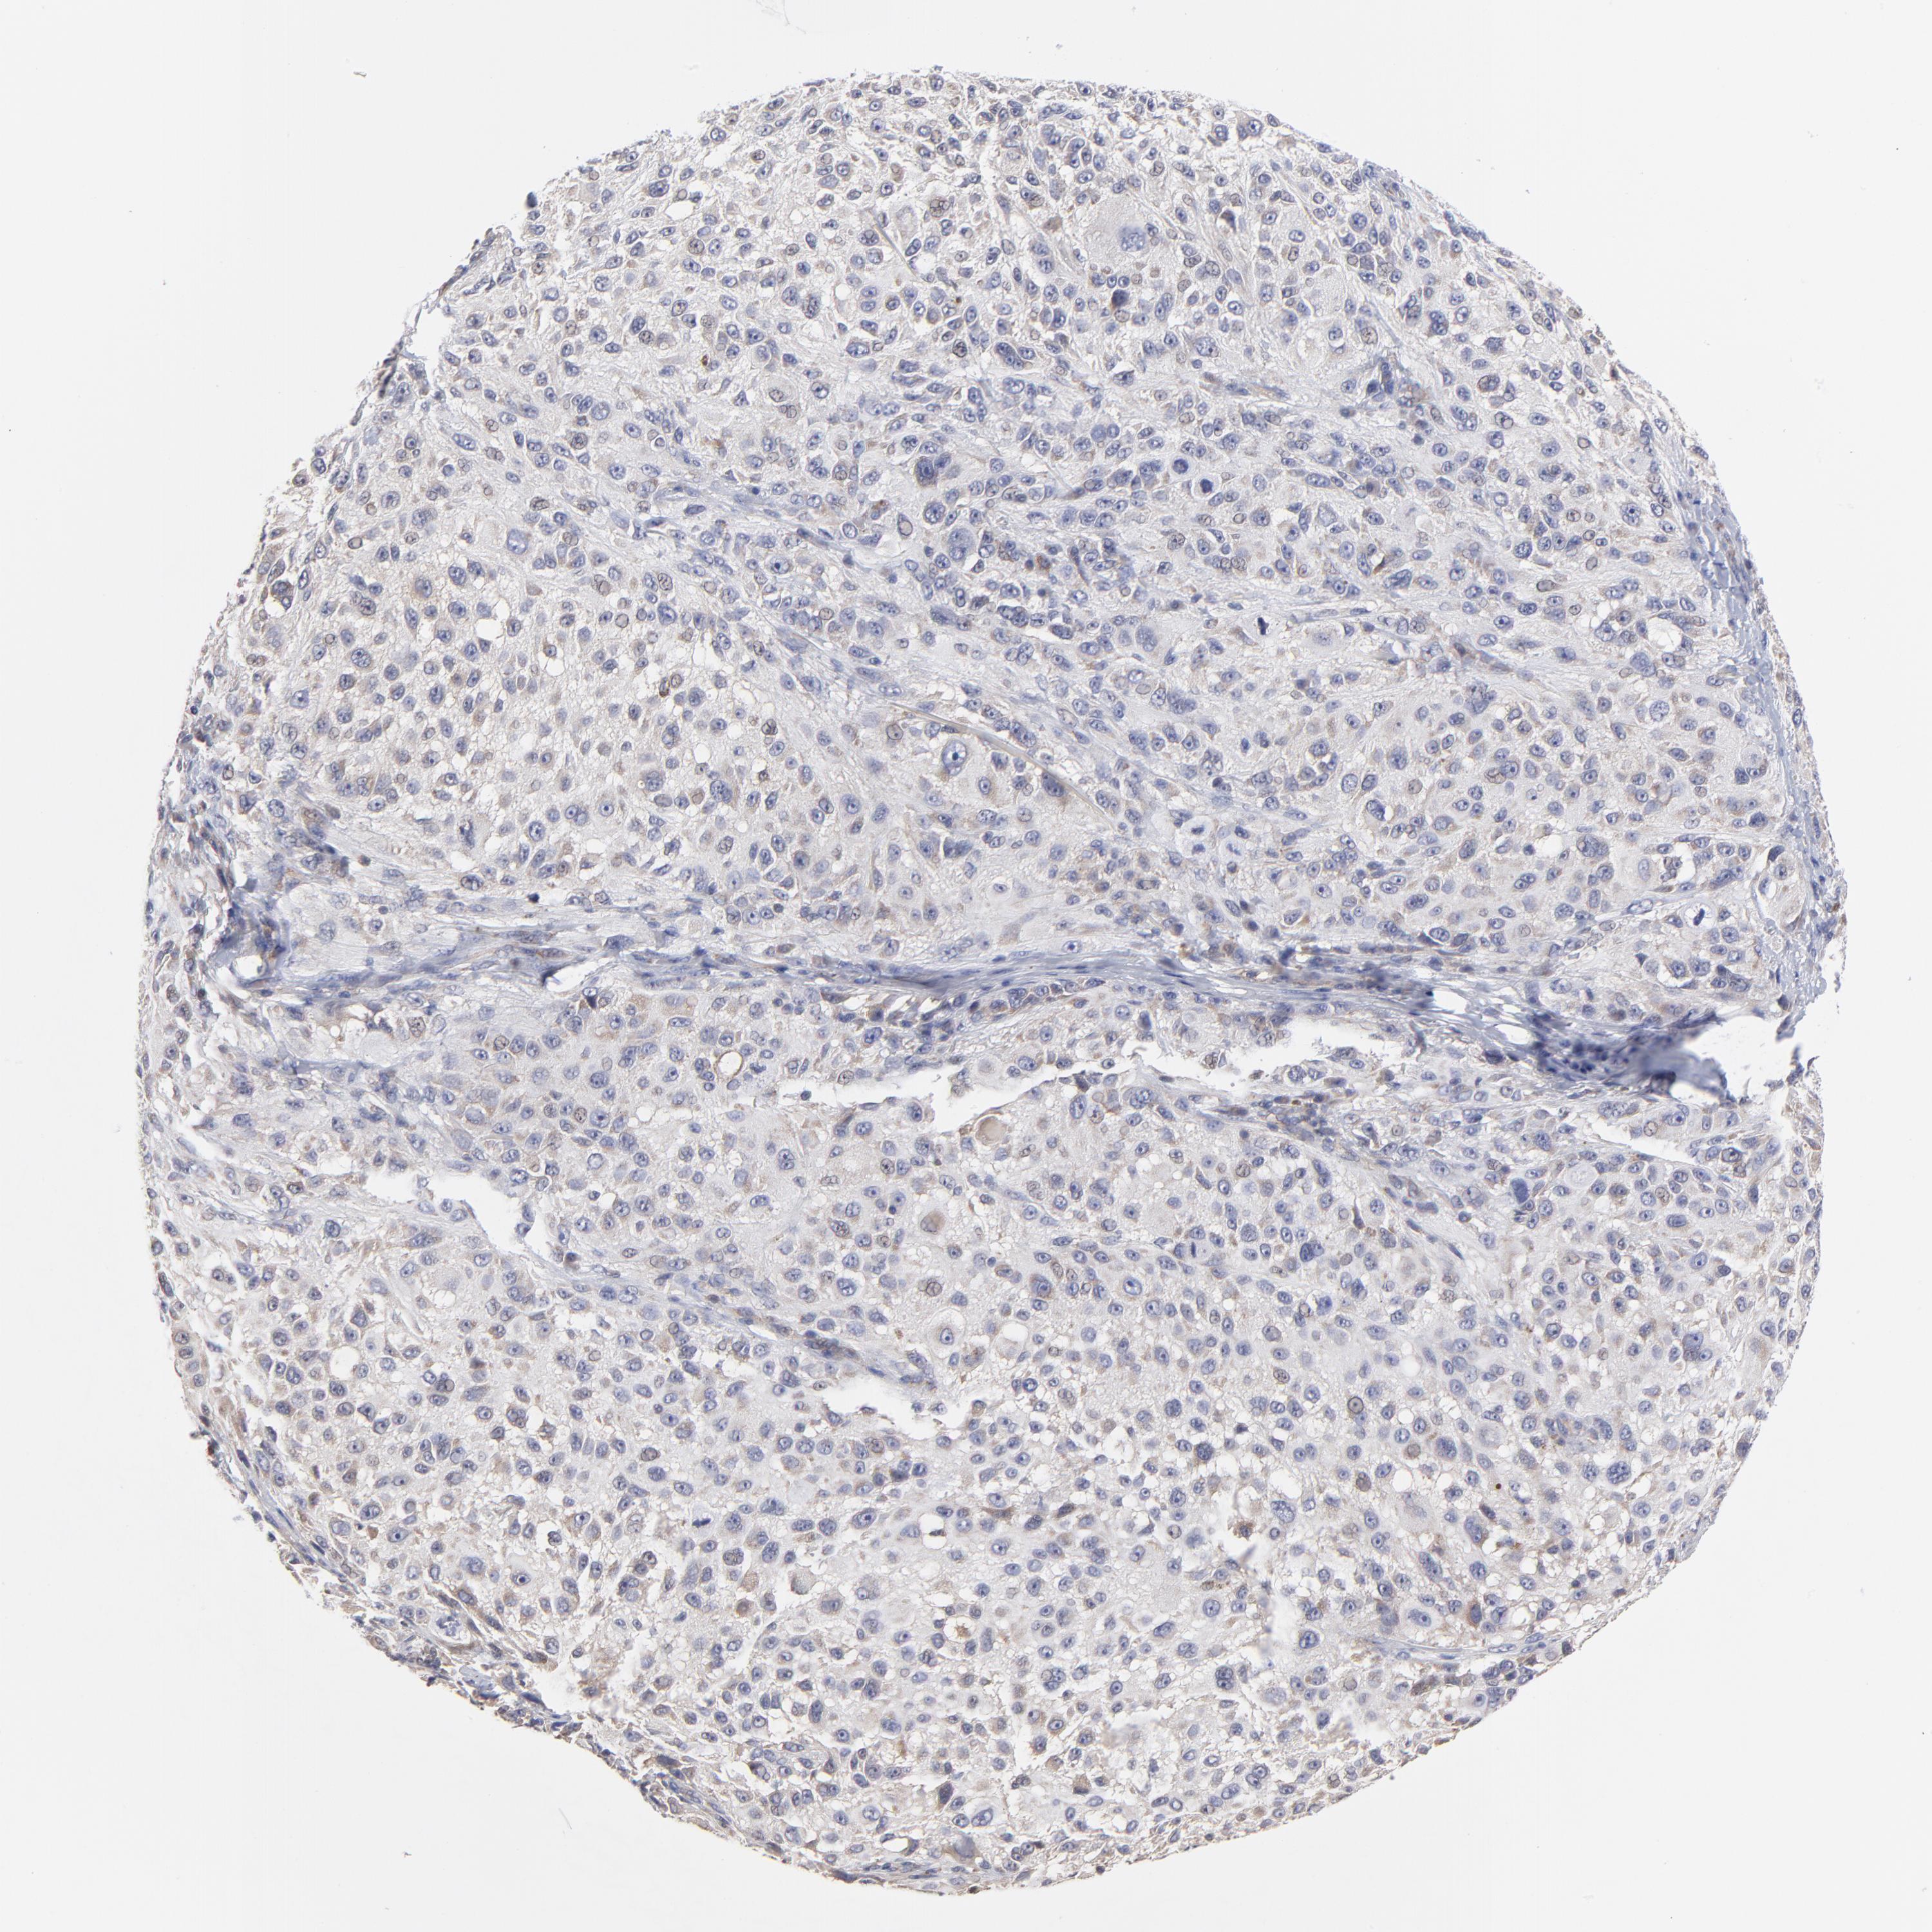

MELANOMA - Protein expressioni

A mouse-over function shows sample information and annotation data. Click on an image to view it in a full screen mode. Samples can be filtered based on level of antibody staining by selecting one or several of the following categories: high, medium, low and not detected. The assay and annotation is described here.

Note that samples used for immunohistochemistry by the Human Protein Atlas do not correspond to samples in the TCGA dataset.

Antibody stainingi

Antibody staining in the annotated cell types in the current human tissue is reported as not detected, low, medium, or high, based on conventional immunohistochemistry profiling in selected tissues. This score is based on the combination of the staining intensity and fraction of stained cells.

Each image is clickable and will lead to virtual microscopy that enables deeper exploration of all samples and also displays staining intensity scores, fraction scores and subcellular localization as well as patient and tissue information for each sample.

Antibody HPA003319

Staining

High

Medium

Low

Not detected

Intensity

Strong

Moderate

Weak

Negative

Quantity

>75%

75%-25%

<25%

None

Location

Nuclear

Cytoplasmic/membranous

Cytoplasmic/membranous,nuclear

Malignant melanoma, NOS

Malignant melanoma, Metastatic site